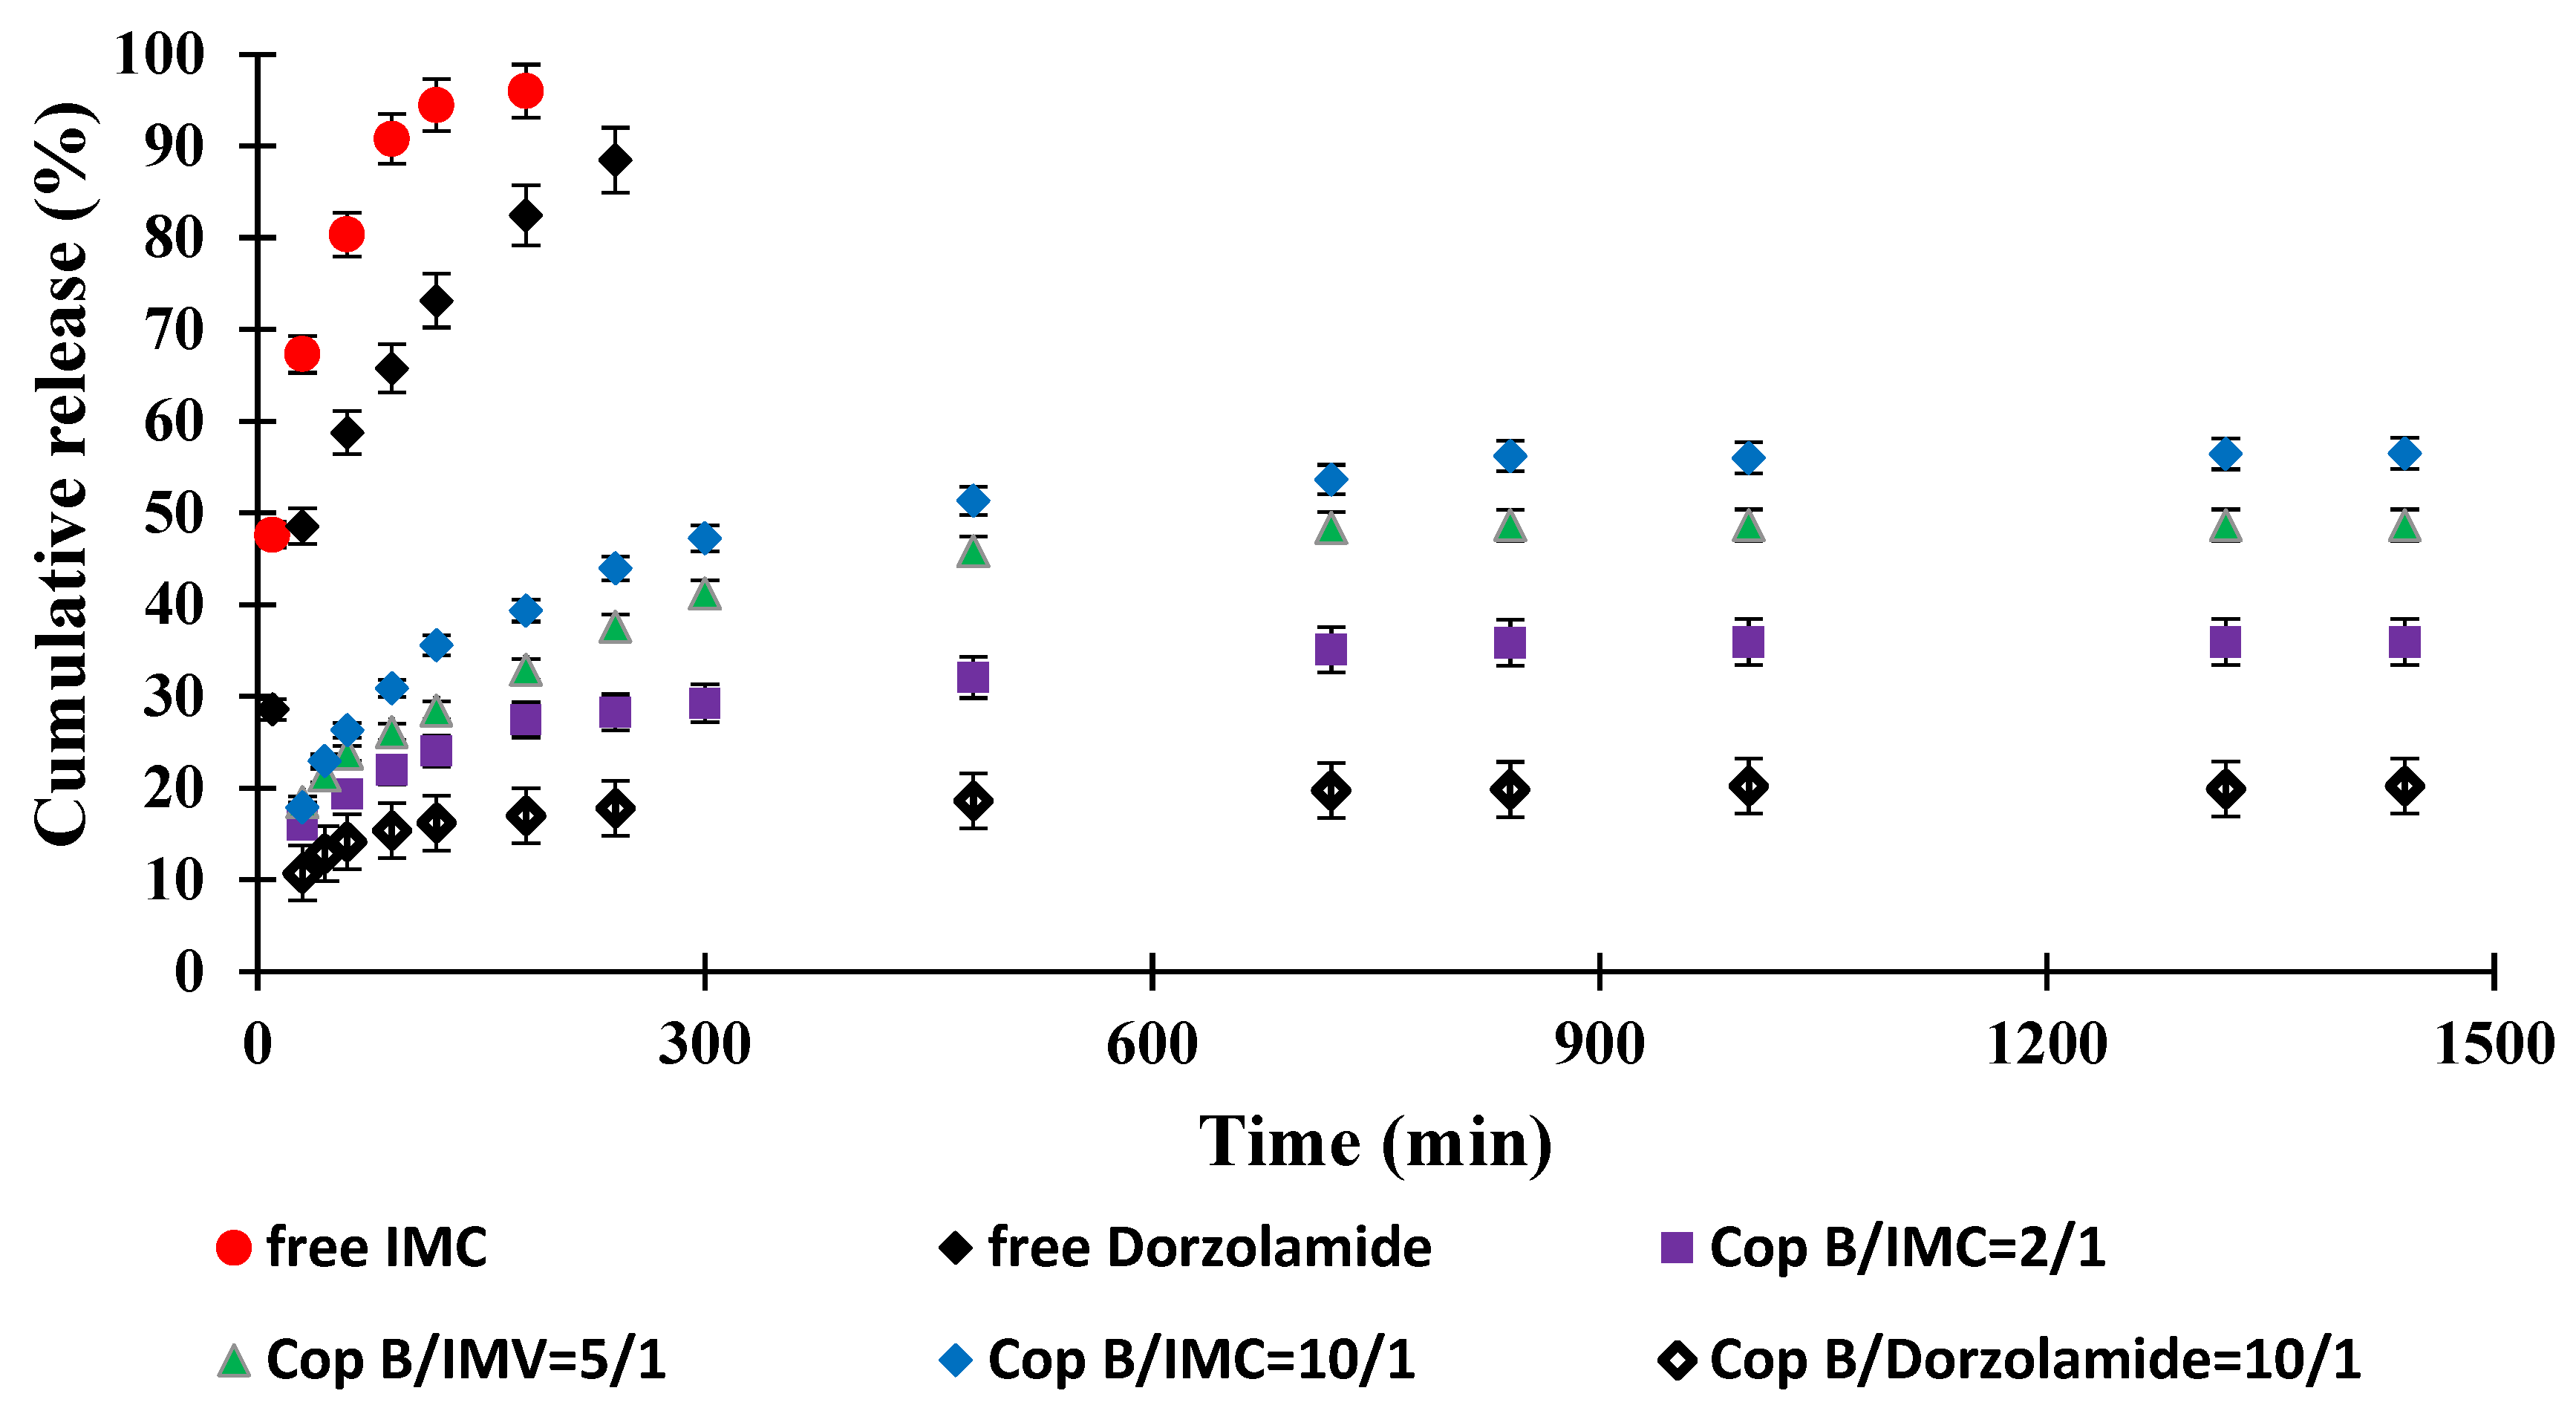

2.5. Drug Release Kinetics